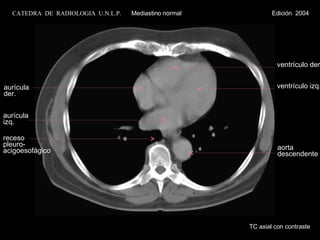

aurícula der. aurícula izq. ventrículo der. ventrículo izq. receso pleuro- acigoesofágico TC axial con contraste aorta descendente CATEDRA  DE  RADIOLOGIA  U.N.L.P.   Mediastino normal  Edición  2004

aurícula der. aurículaizq. ventrículo der. ventrículo izq. receso pleuro- acigoesofágico TC axial con contraste aorta descendente CATEDRA DE RADIOLOGIA U.N.L.P. Mediastino normal Edición 2004